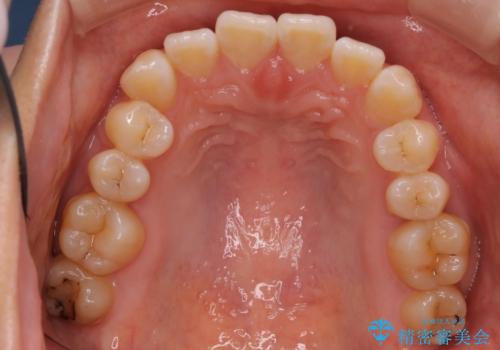

- 患者様は、右下第2小臼歯(5番)の先天欠如により乳歯が残存している状態でした。

加えて、**下顎前歯部に叢生(歯のがたつき)**が見られ、審美的・機能的な改善を希望されて来院されました。

診査の結果、乳歯は長期間機能していましたが、将来的な脱落のリスクが高く、インプラントによる永久歯の補綴が望ましいと判断しました。

また、欠損部にインプラントを埋入するには、前後の歯の傾斜改善とスペース確保のための矯正治療が必要でした。

下顎前歯の叢生も同時に改善できるよう、全体的なワイヤー矯正による治療計画を立案しました。